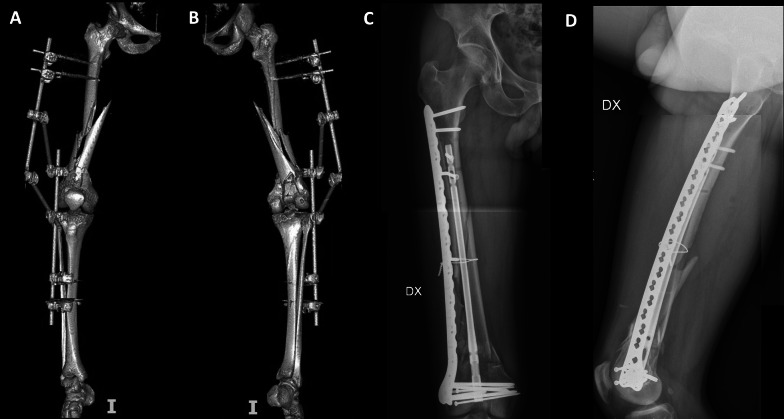

背景:股骨远端骨折是骨科医生面临的一个重大挑战,约占所有股骨骨折的5%。文献中最常报道的联合技术是双钢板技术和逆行钉入加侧钢板,即钉-钢板结构(NPC)。本研究的目的是比较双钢板或逆行内钉加侧钢板治疗33-C骨折的手术数据、生活质量和功能结果。材料和方法:根据加强流行病学观察性研究报告(STROBE)指南进行多中心回顾性观察性研究。诊断是基于AO分类,利用传统的放射学评估。根据患者接受的手术治疗将患者分为两组:NPC组包括接受钉子-钢板结构手术的患者,而Plate组包括接受双钢板手术的患者。结果:共纳入42例患者。鼻咽癌组26例,平均年龄58.4±18.8岁;钢板组16例,平均年龄61.3±16.4岁。在膝关节伸展恢复(p = 0.010)和股骨远端外侧角度(LDFA)方面观察到显著差异(p)。结论:在AO型C型股骨远端骨折中,与双钢板相比,钉钢板结构在膝关节功能和生活质量方面似乎具有明显更好的结果。解剖结果也显示出显著差异,特别是伸展间隙和LDFA。证据水平:III。

Background: Distal femur fractures present a significant challenge for orthopedic surgeons, accounting for approximately 5% of all femoral fractures. Among the most commonly reported combined techniques in the literature are the double-plate technique and the retrograde nailing plus lateral plating, the nail-plate construct (NPC). The aim of our study is to compare surgical data, quality of life, and functional outcomes in 33-C fractures treated with either double-plate constructs or a retrograde nailing plus lateral plate.

Materials and methods: A multicenter retrospective observational study was conducted in accordance with Strengthening the Reporting of Observational Studies in Epidemiology (STROBE) guidelines. Diagnoses were made on the basis of the AO classification, utilizing traditional radiological assessments. Patients were categorized into two groups on the basis of the surgical treatment they received: The NPC group comprised patients who underwent surgery with nail-plate construct, while the Plate group consisted of those who had surgery with double plating.

Results: A total of 42 patients were included in the study. The NPC group comprised 26 patients with a mean age of 58.4 ± 18.8 years, while the Plate group consisted of 16 patients with a mean age of 61.3 ± 16.4 years. Significant differences were observed in knee extension recovery (p = 0.010) and lateral distal femur angle (LDFA) (p < 0.001). Linear regression showed a significant influence from treatment choice on all the Knee Injury and Osteoarthritis Outcome Score (KOOS) subscales, as well as in all domains of the European Quality of Life Five Dimensions Five-Level Version (EQ-5D-5L), except for the Daily Self-Care domain.

Conclusions: Nail-plate constructs seems to lead to significantly better outcomes in AO type C distal femur fractures, compared with double plating, in terms of knee function and quality of life. Significant differences are shown also in anatomical outcomes, especially in extension gap, and LDFA.